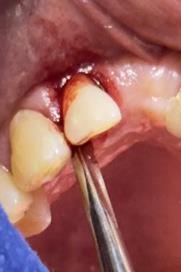

Sindesmotomía con un periostótomo de molt # 9, posteriormente se realizó la luxación con un elevador recto, buscando el punto de apoyo, seguido se efectuó la prensión con el fórceps 150 en el diente con sumo cuidado de no tocar la encía colocándolo hasta el cuello dental, haciendo movimientos de lateralidad y rotación hasta lograr la dilatación del alveolo, y finalmente la tracción del órgano dentario, observando que la raíz este integra, y que estructuras alrededor estén conservadas, de la misma forma se revisó el alveolo en busca de la presencia de granulomas o espículas óseas, una vez ya revisado se procedió al curetaje, con una cucharilla de lucas, se introdujo y se dio paso al retiro del exudado purulento, se realizó irrigación del alveolo con solución fisiológica, una vez limpio se realizó una sutura simple con sutura nylon, seda # 3/0 en el medio del alveolo con la finalidad de aproximar rebordes, evitar su contaminación por el ingreso de comida, además generar una mejor cicatrización en una zona estética , finalmente se aplicó presión por medio de una gasa que mordió el paciente por un lapso de 30 minutos, para contribuir con una hemostasia adecuada.

Figura 6. Sindesmotomía, luxación y prensión del incisivo lateral superior derecho pieza N.º 1.2

Elaboración: Los autores.